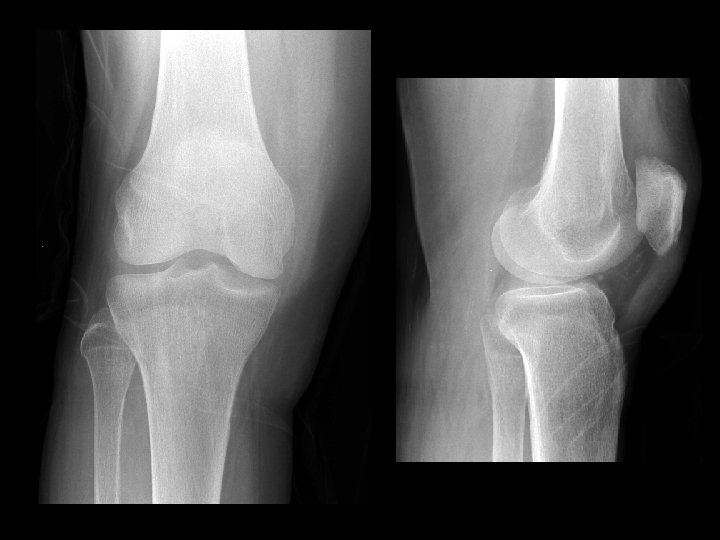

Inflammatory Arthritis • • Findings: – Severe joint space narrowing – Sub-chondral cystic changes and sclerosis – No significant osteophyte formation ddx: – Post-infectious